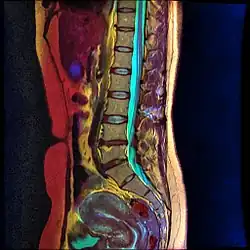

Magnetic resonance image of lumbar spine

Lumbar sympathetic neurolysis is typically used on patients with ischemic rest pain, generally associated with nonreconstructable arterial occlusive disease. Although the disease is the basis for this type of neurolysis, other diseases such as peripheral neuralgia or vasospastic disorders can receive lumbar sympathetic neurolysis for pain treatment.[13]

Lumbar sympathetic neurolysis is performed between the L1-L4 vertebrae with separate injections at each vertebra junction. The chemicals used for neurolysis of the nerves cause destructive fibrosis and cause a disruption of the sympathetic ganglia. The vasomotor tone is decreased in the area affected by the neurolysis, which in addition to arteriovenous shunting, create a light pink appearance within the affected area. Lumbar sympathetic neurolysis alters the ischemic rest pain transmission by changing norepinephrine and catecholamine levels or by disturbing afferent fibers. This procedure is mainly used only when other feasible approaches to pain management are unable to be used.[13]

Lumbar sympathetic neurolysis is performed by using absolute alcohol, but other chemicals such as phenol, or other techniques such as radiofrequency or laser ablation have been studied. To aid in the procedure, fluoroscopy or CT guidance is used. Fluoroscopic guidance is the most frequent, giving better real-time monitoring of the needle. The general technique of administering lumbar sympathetic neurolysis involves using three separate needles rather than one because it allows for better longitudinal spread of the chemicals.[13]

Complications can arise from this procedure such as nerve root injury, bleeding, paralysis, and more. Complications have been seen to be diminished when using the aforementioned radiofrequency or laser ablation techniques in comparison to the injection of alcohol or phenol. Generally, approximately two-thirds of patients can expect a favorable outcome (pain relief with minimal complications). Overall, the minimally invasive technique of lumbar sympathetic neurolysis is important in the relief of ischemic rest pain.[13]